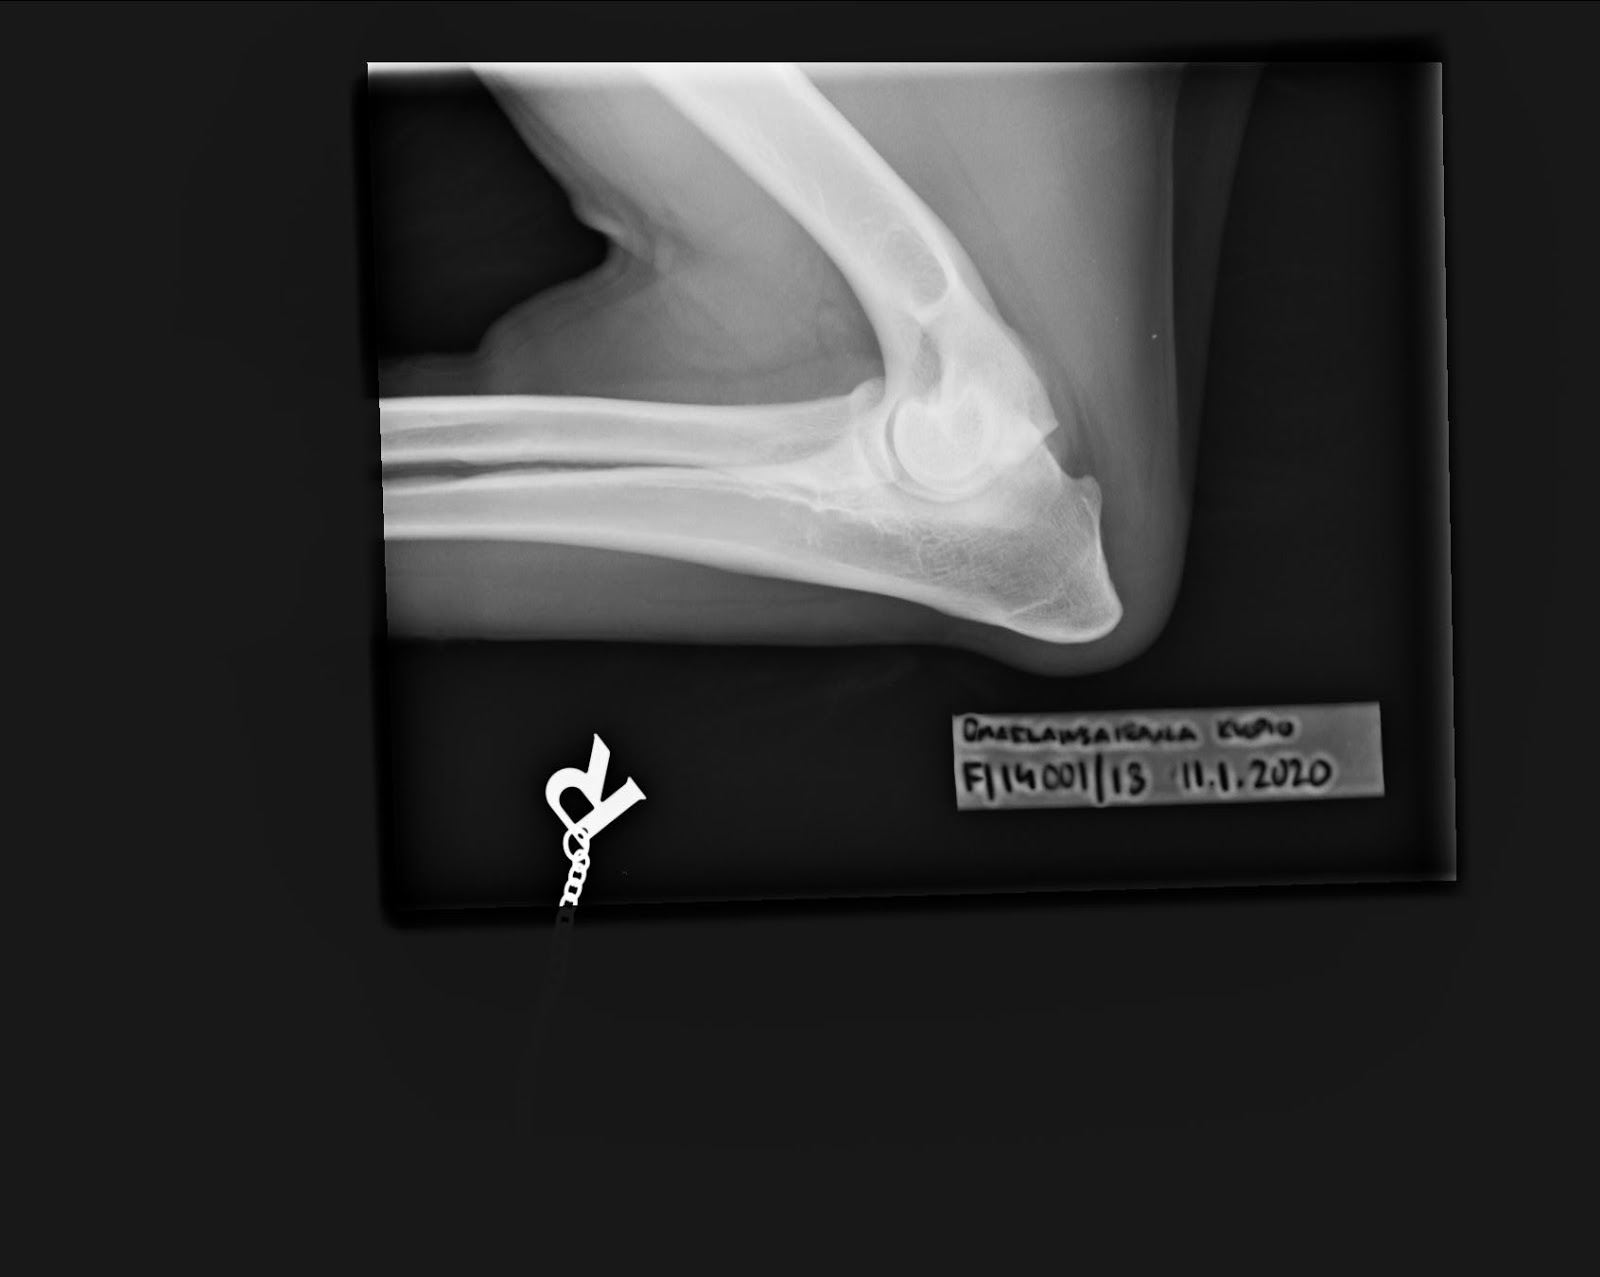

Loppuilta kului hieman sumussa, lonkkien kanssa oli taas vaikeuksia saada suoraa kuvaa, eikä toinen polvi tuntunut vääntyvän millään samaan suuntaan kuin toinen. Kanssamme kuvaava lääkäri sitten tuumi että siinäkin on jotain, emme kuitenkaan harmikseni kuvanneet niistä sivukuvia, olimmehan kaikki jo väsyneitä ja kukin tavoillamme yllättyneen järkyttyneitä selän muutoksista, näkyihän rintarangassakin jo alkavia siltoja. Kyynäriä emme edes tarkemmin katselleet, tulee mitä tulee, pientä höttöisyyttä kyllä oli havaittavissa etenkin junnuiän kuviin verraten.

Kyynärnivelissä on kennelliiton mukaiset löydökset. Todennäköisin syy

muutoksille on medial coronoid disease eli mediaalisen varislisäkkeen

ongelma. Tämänkin varmistaminen vaatisi tietokonetomografiakuvauksen ja

diagnoosi/hoito tähystyksen. Varislisäkkeen ongelmat johtavat usein

tähystyksestä huolimattakin etenevään nivelrikkoon.